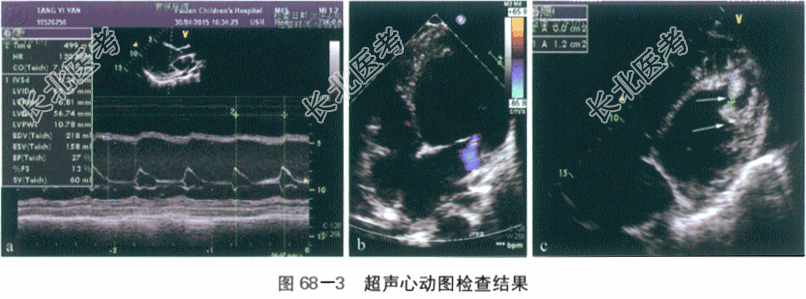

(3)超声心动图检查(2015年4月30号):心房正位,房-室连接、心室-大动脉连接正常。左心房内径35mm,左心室内径舒张末期(LVEDD)65mm,收缩末期(LVESD)56mm,主肺动脉内径27mm,主动脉根部内径18mm,室间隔与左室后壁均为6mm。全心增大,以左房、左室内径增大为著,心脏搏动明显减弱,LVEF=27%(见图68-3-a)。房间隔与室间隔完整。肺动脉增宽,肺动脉瓣轻度反流,主动脉瓣启闭正常;二、三尖瓣探及轻度反流(见图68-3-b),三尖瓣反流压差37mmHg,多普勒组织成像(DTI)测二、三尖瓣E/A均>1。左室心腔内紧心尖处探及两个中高回声团块,面积分别为2cm

和3.6cm

,考虑为血栓形成(见图68-3-c,白色箭头)。主动脉弓左位,形态和血流未见异常。左、右冠状动脉起源未见异常。下腔静脉呈淤血扩张状。结论:①全心增大,以左心增大为主,心功能不全LVEF27%;②左室内附壁血栓可能;③二尖瓣轻度反流;④肺动脉高压(轻度)。如图68-3所示。

2015年5月18日复查:①左室内径显著增大,LVEDD61mm,LVESD49mm,心功能不全LVEF40%;②左室内占位基本消失;③二尖瓣反流(轻度);④肺动脉高压(轻度)。 (4)24h动态心电图:①窦性心动过速。②单一形态室性早搏1823次/24h,见6对成对出现。③ST-T段改变。④QRS电交替。 (5)心脏及大动脉计算机断层血管造影(CTA):心影增大,左室为著,左室内壁毛糙;主动脉弓未见明显异常;冠状动脉起源未见异常。如图68-4所示。